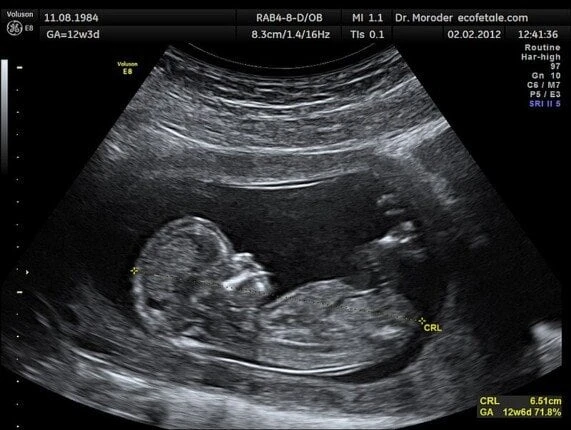

قالت هيئة الدواء المصرية: إن الموجات فوق الصوتية (السونار)، هي تقنية سريعة وغير مؤلمة للتصوير تنتج صورة للأعضاء الداخلية من خلال استخدام موجات صوتية ذات تردد عالي، مشيرة إلى أنه لا توجد أي أعراض جانبية لهذا الفحص.

وأوضحت هيئة الدواء، أنه بالرغم من أن كثير من فحوصات الموجات فوق الصوتية لا تحتاج إلى تجهيزات، فإن بعضها يحتاج إلى الصيام لمدة 6 ساعات قبل الفحص، بالإضافة إلى المرضى اللذين يقومون بعمل أشعة الموجات فوق الصوتية على الرحم، المبايض أو البروستاتا مطلوب أن تكون المثانة البولية ممتلئة لأن ذلك يسهم فى رؤية تلك الأعضاء بسهولة.

وأضافت الهيئة أن الطبيب قد يوصي بفحص الموجات فوق الصوتية للمساعدة فيما يلي:

- تصوير ومتابعة الجنين أثناء الحمل.